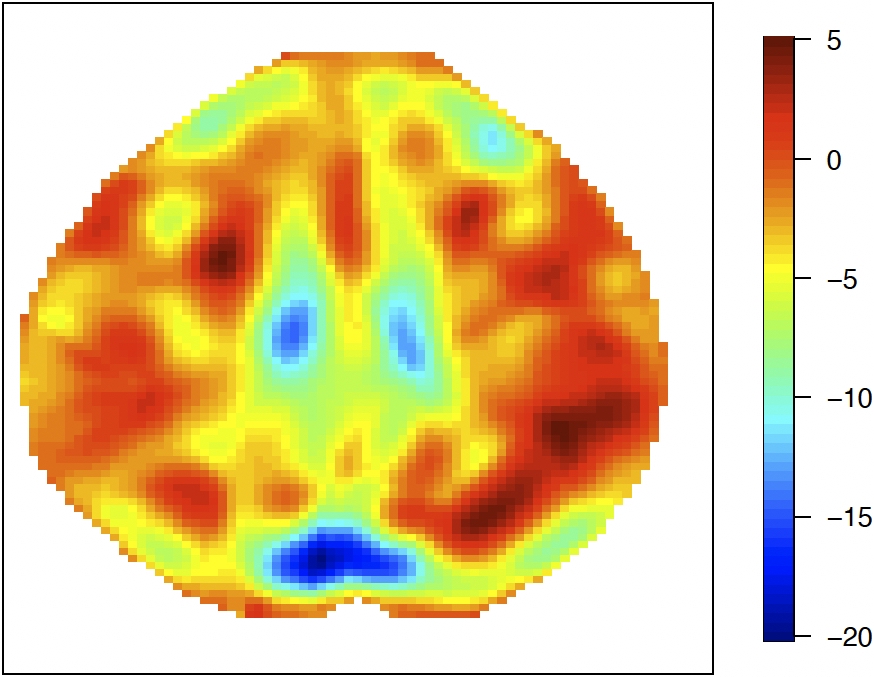

For the Hilbert-valued component, we first consider a 2D imaging setting. To mimic the full complexity of the real data and illustrate the performance of the proposed method in a challenging scenario with complicated patterns, we use the leading empirical basis functions obtained from the real data analysis in Section 6. To be specific, we construct the imaging data as Zi(s1,s2)=j=16λj1/2Uijϕj(s1,s2)Z_{i}(s_{1},s_{2})=\sum_{j=1}^{6}\lambda_{j}^{1/2}U_{ij}\phi_{j}(s_{1},s_{2}) on a 79×9579\times 95 pixel grid, where the eigenvalues (λ1,λ2,λ3,λ4,λ5,λ6)=(3.5,3,2.5,2,1.5,1)(\lambda_{1},\lambda_{2},\lambda_{3},\lambda_{4},\lambda_{5},\lambda_{6})=(3.5,3,2.5,2,1.5,1) and (Ui1,,Ui6)(U_{i1},\ldots,U_{i6})^{\top} follows MVN(06,I6)\text{MVN}(0_{6},I_{6}). The basis functions {ϕj}j=16\{\phi_{j}\}_{j=1}^{6} are the leading six principal component bases that are selected by PVE from the real data analysis; see Section 6.1 for more details. Figure 5.1 (top row) and Figure 6.1 (left three columns) display the plots of these basis functions. We set γ0=1.5ϕ1+ϕ2+2ϕ3+2.5ϕ4+1.5ϕ5+3ϕ6\gamma_{0}=1.5\phi_{1}+\phi_{2}+2\phi_{3}+2.5\phi_{4}+1.5\phi_{5}+3\phi_{6}.

Refer to caption Refer to caption Refer to caption Refer to caption Refer to caption Refer to caption

ϕ1\phi_{1}\penalty 10000\ \penalty 10000\ ϕ2\phi_{2} ϕ3\phi_{3} ϕ4\phi_{4}\penalty 10000\ \penalty 10000\ ϕ5\phi_{5} ϕ6\phi_{6}

ϕ^1\widehat{\phi}_{1}\penalty 10000\ \penalty 10000\ ϕ^2\widehat{\phi}_{2} ϕ^3\widehat{\phi}_{3} ϕ^4\widehat{\phi}_{4}\penalty 10000\ \penalty 10000\ ϕ^5\widehat{\phi}_{5} ϕ^6\widehat{\phi}_{6}

Figure 5.1: Comparison of true basis functions {ϕj}j=16\{\phi_{j}\}_{j=1}^{6} (top) and their estimates {ϕ^j}j=16\{\widehat{\phi}_{j}\}_{j=1}^{6} (bottom) for a randomly selected iteration with n=2000n=2000 in the 2D imaging setting.

The estimates of the basis functions are shown at the bottom of Figure 5.1, which is selected randomly from a single iteration. The figure shows that with n=2000n=2000 observations, the estimated basis functions (bottom row) closely reproduce both the pattern and magnitude of the true functions (top row), providing empirical validation of Theorem 4. In addition, Table 5.1 presents the estimation accuracy of the six eigenvalues (λ1\lambda_{1} through λ6\lambda_{6}) and the estimated number of eigenvalues under the PVE (m^n\widehat{m}_{n}) criterion. We observe that MSEs for all eigenvalues decrease as sample size increases across both correlation scenarios, demonstrating improved estimation precision with larger samples. The results in Table 5.1 further support the conclusions in Theorem 4 and Corollary 3.